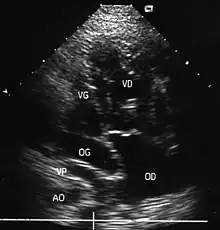

- Les coupes échographiques les plus utiles à cette fin sont :

- la coupe parasternale gauche grand axe : elle montre que le vaisseau issu du ventricule gauche (le plus postérieur) se dirige anormalement vers l'arrière et se bifurque précocement. C'est donc le tronc pulmonaire et non l'aorte comme normalement ;

- les coupes sous costales qui montrent bien le trajet parallèle des gros vaisseaux et leur inversion.